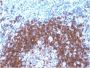

Positive Control

MCF-7 cells or Cervical carcinoma

IHC, FFPE (verified), WB (verified)

IHC (FFPE) (verified)|WB (verified)

Higher concentration may be required for direct detection using primary antibody conjugates than for indirect detection with secondary antibody|Immunofluorescence: 1-2 ug/mL|ELISA: 2-4 ug/mL for coating order Ab without BSA|Immunohistology (formalin): 0.5-1 ug/mL|Staining of formalin-fixed tissues requires boiling tissue sections in 10 mM citrate buffer, pH 6.0, for 10-20 min followed by cooling at RT for 20 min|Flow Cytometry 0.5-1 ug/million cells/0.1 mL|Western blotting 0.5-1 ug/mL|Optimal dilution for a specific application should be determined by user